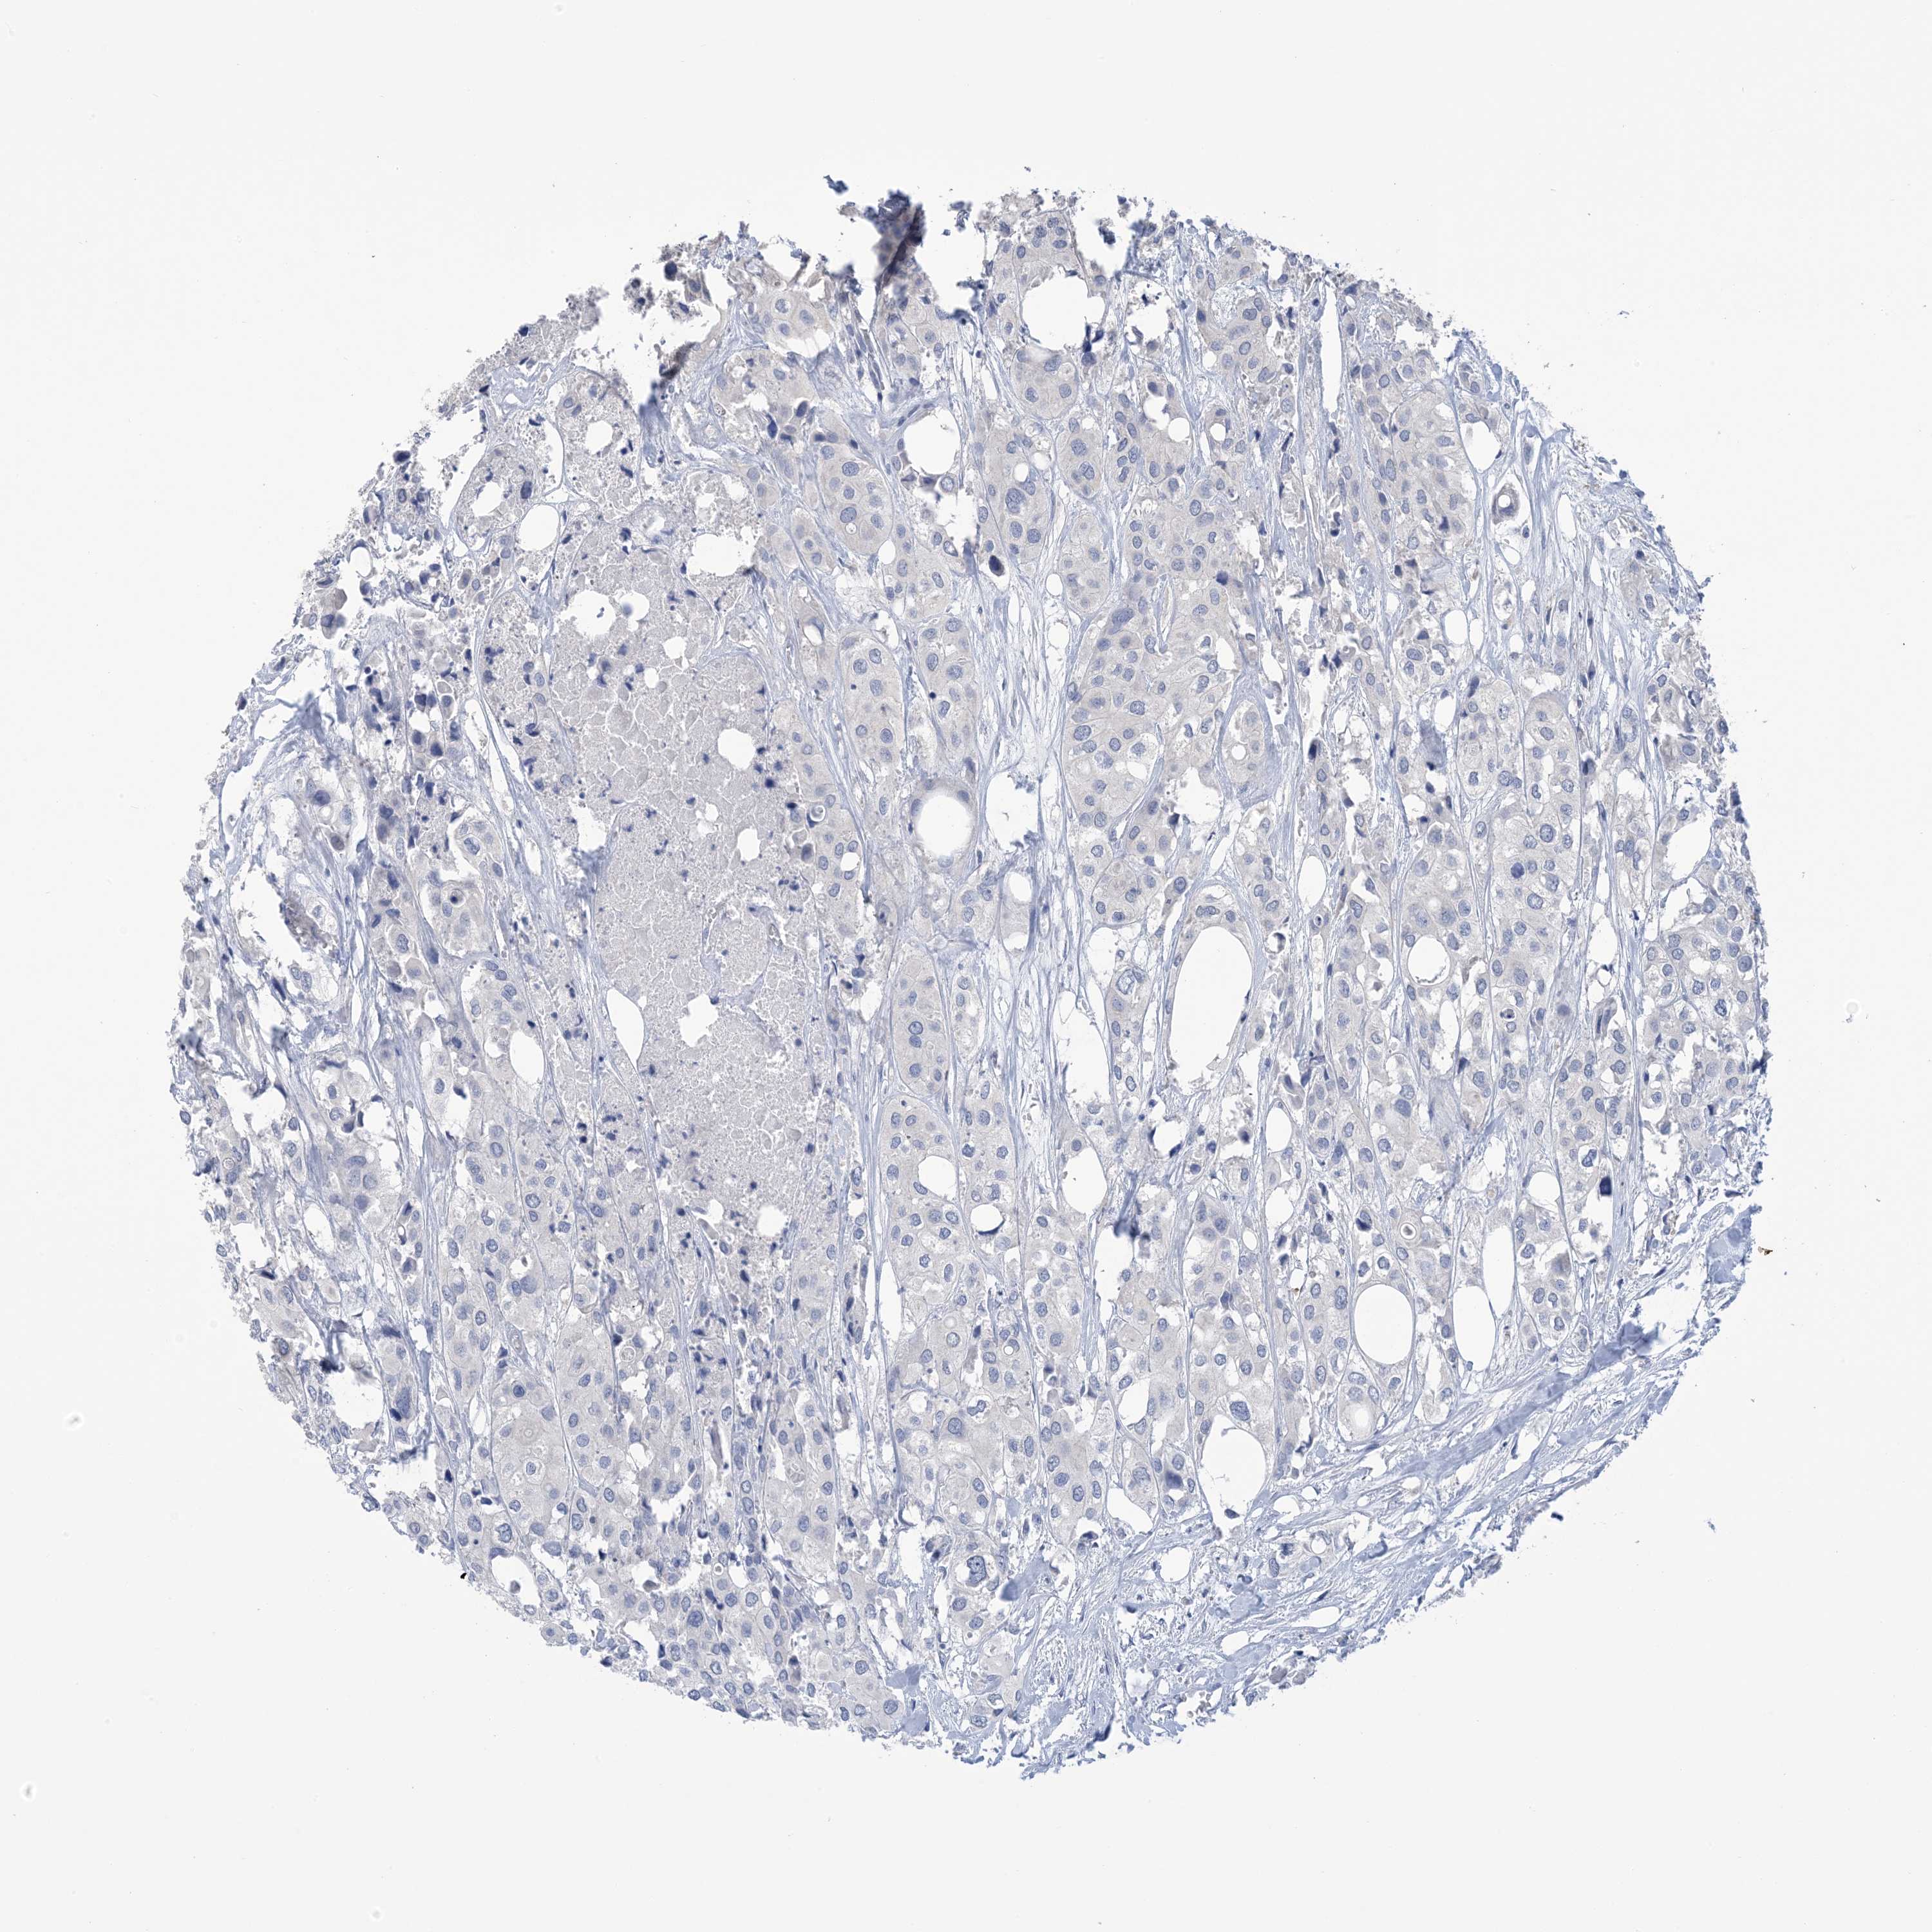

UROTHELIAL CANCER - Protein expressioni

A mouse-over function shows sample information and annotation data. Click on an image to view it in a full screen mode. Samples can be filtered based on level of antibody staining by selecting one or several of the following categories: high, medium, low and not detected. The assay and annotation is described here.

Antibody stainingi

Antibody staining in the annotated cell types in the current human tissue is reported as not detected, low, medium, or high, based on conventional immunohistochemistry profiling in selected tissues. This score is based on the combination of the staining intensity and fraction of stained cells.

Each image is clickable and will lead to virtual microscopy that enables deeper exploration of all samples and also displays staining intensity scores, fraction scores and subcellular localization as well as patient and tissue information for each sample.

Antibody HPA049265

Antibody CAB037328

Urothelial carcinoma, High grade

Urothelial carcinoma, Low grade

Urothelial carcinoma, NOS